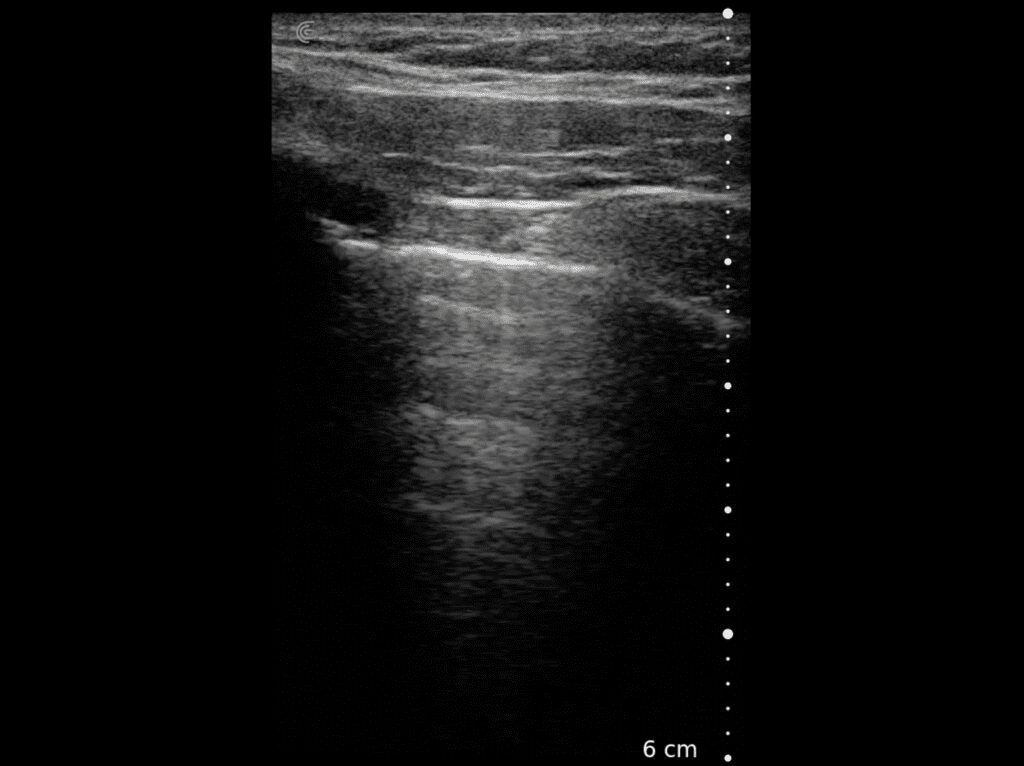

T-Mode es un enfoque innovador para la educación en ecografía diseñado para mejorar sus habilidades de escaneo utilizando la potencia de la inteligencia artificial en aplicaciones de Estética y Cirugía Plástica. Cette technologie novatrice superpose des couleurs distinctes, des motifs et des étiquettes pour identifier et différencier les structures anatomiques et les couches de tissu.